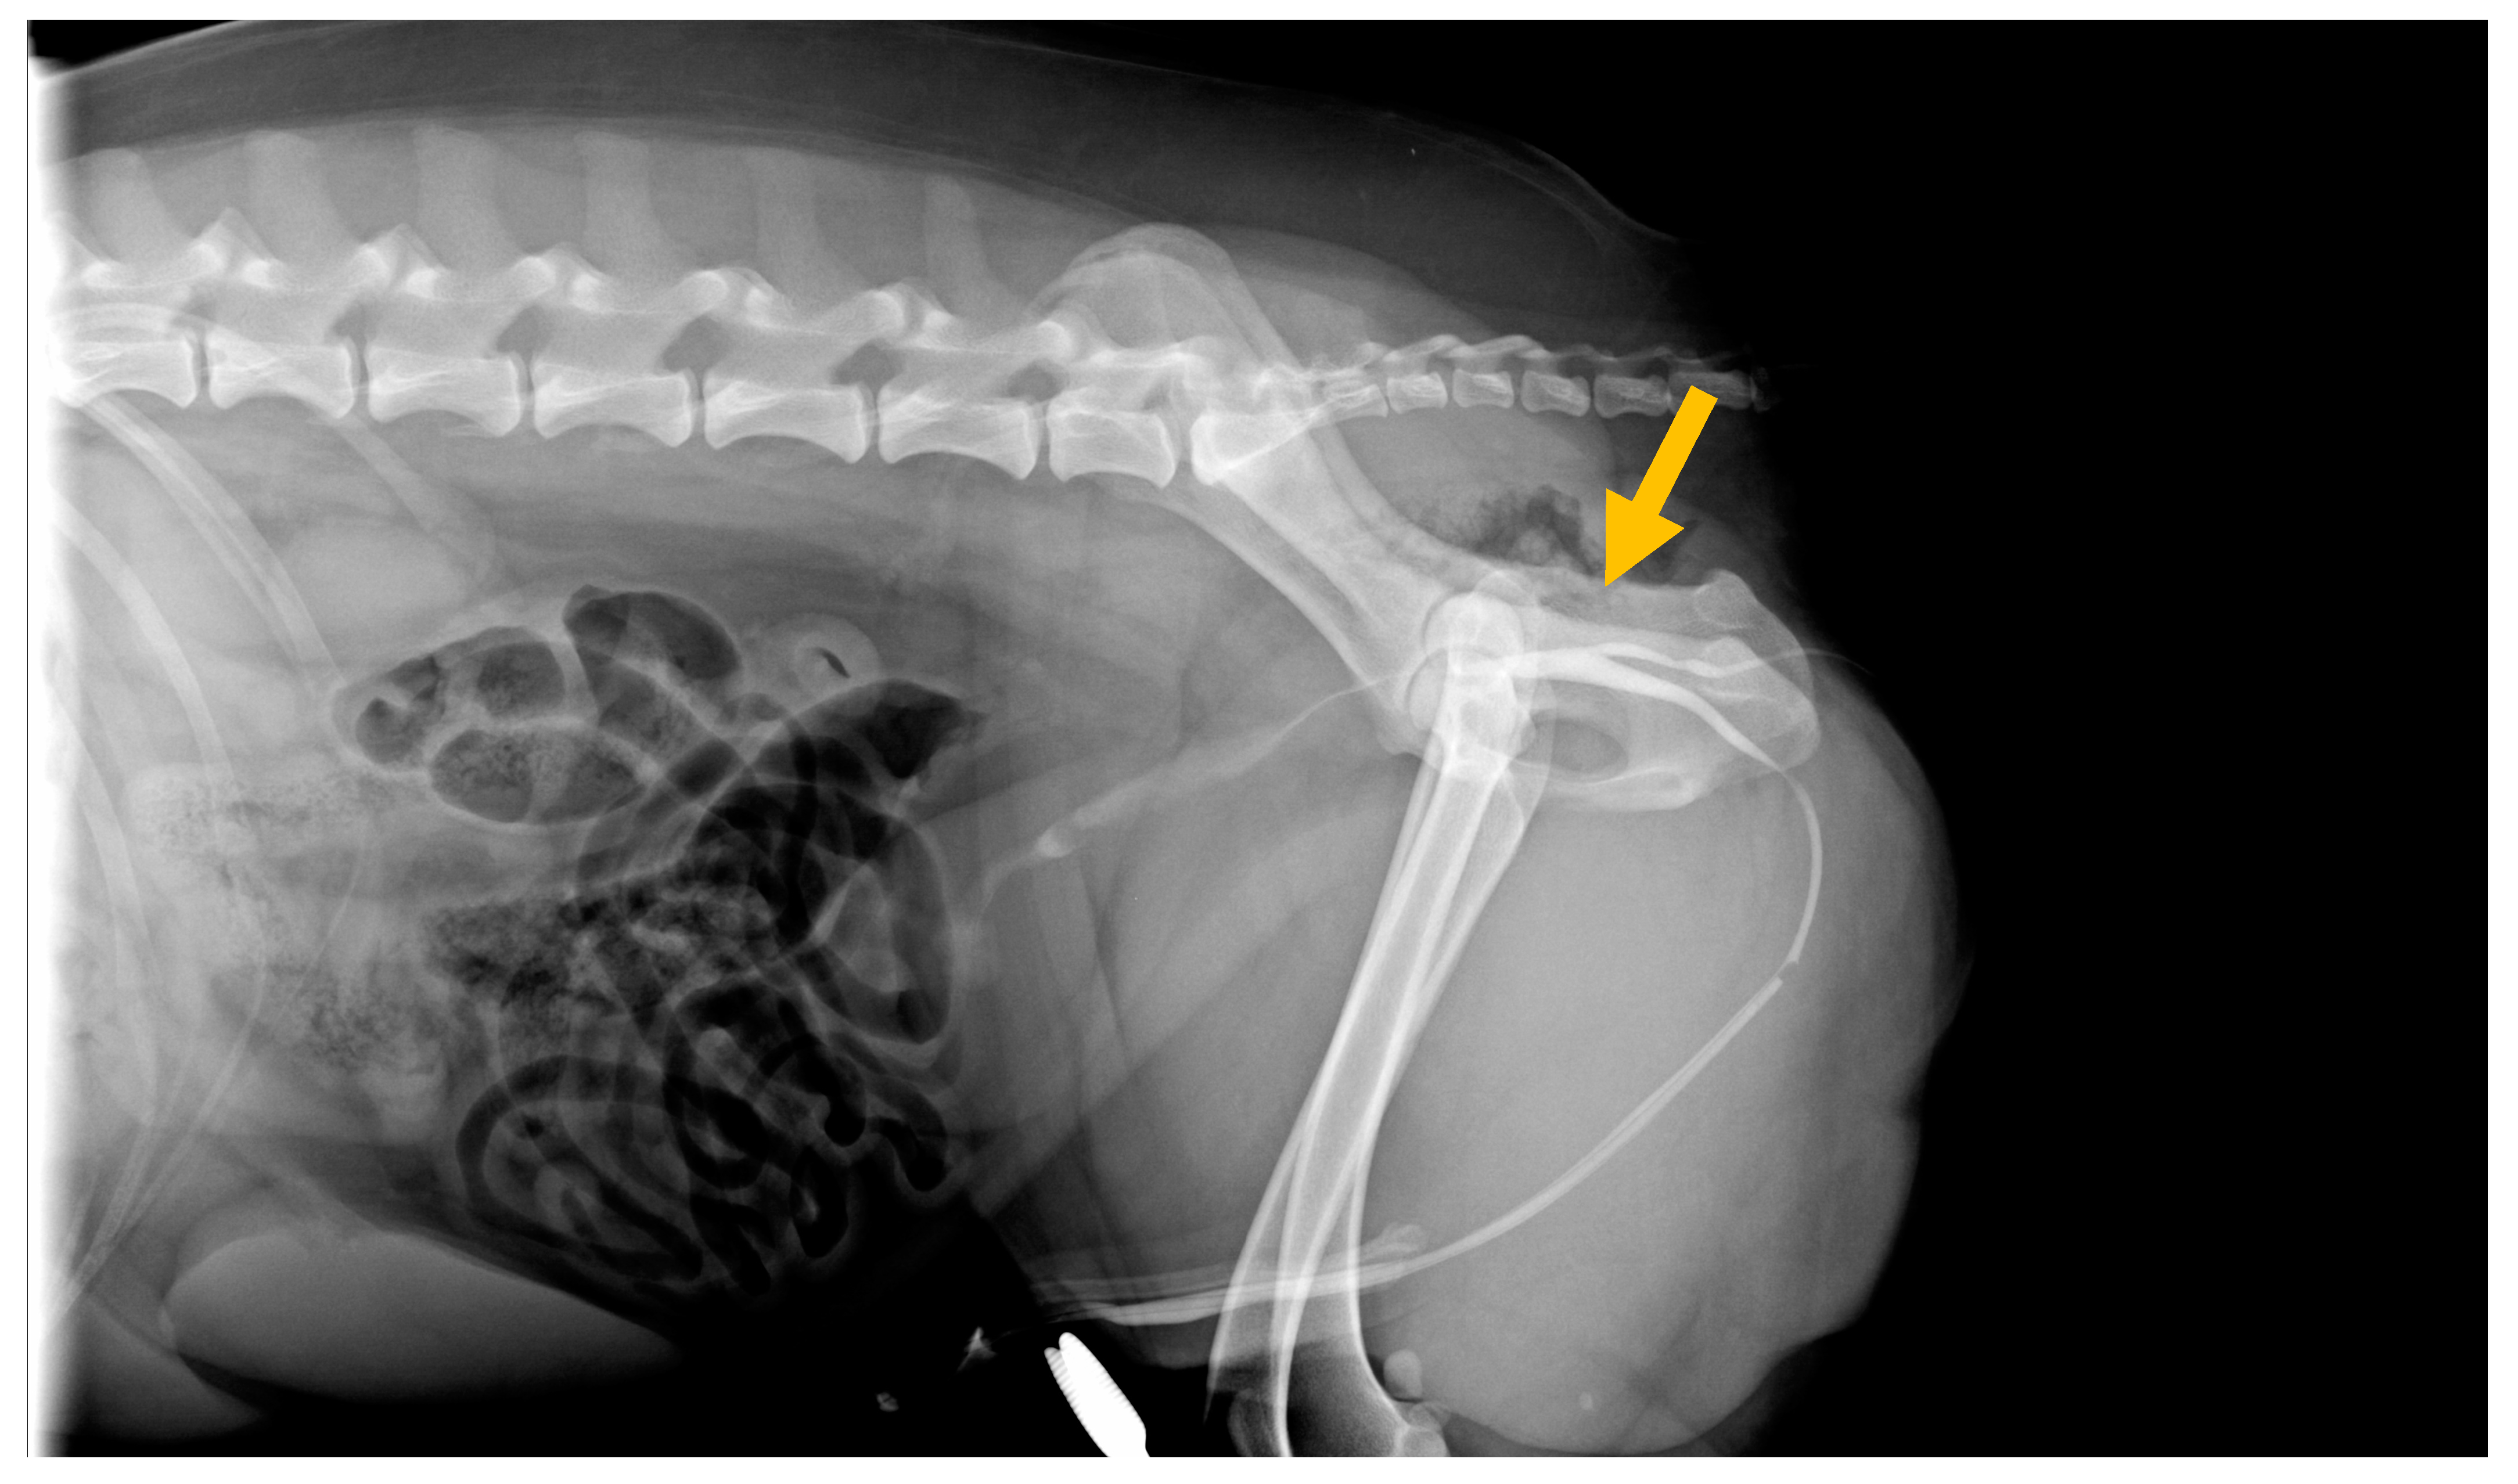

Cystoscopic Guided Laser Cauterization in a Dog with Complete Y-Type Urethral Duplication

2. Case Report